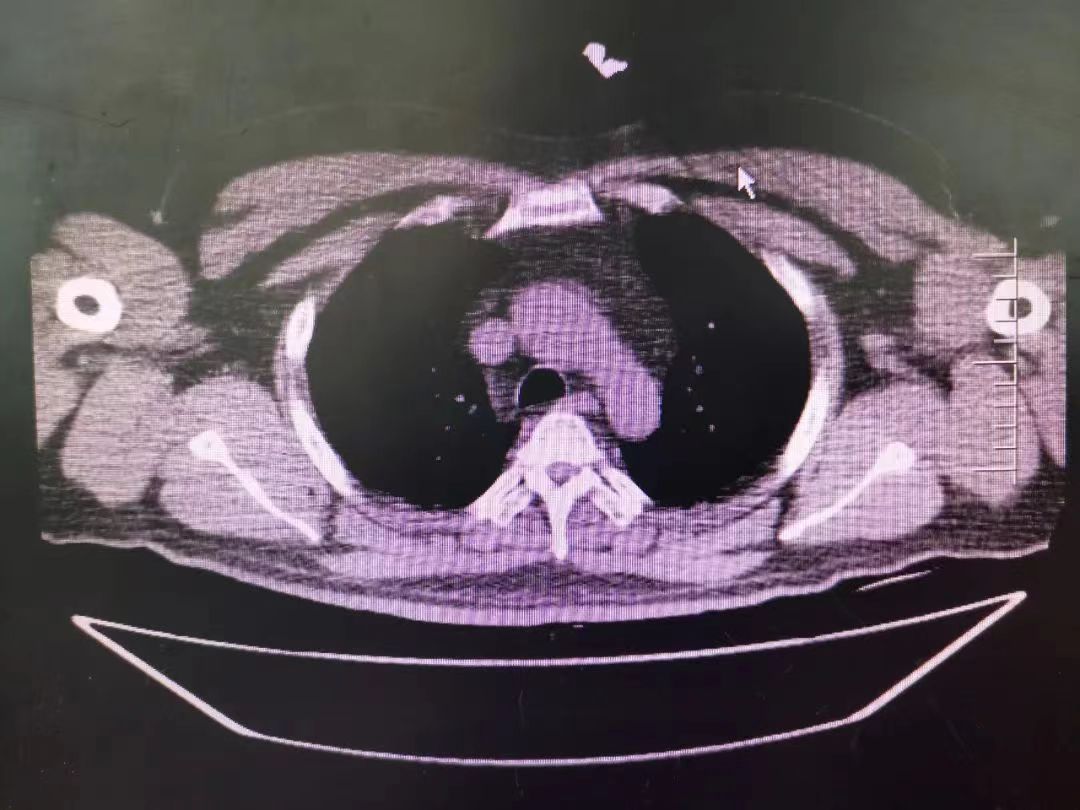

CT室門口,焦燥的家屬不停的走動(dòng)著、等待著,看到醫(yī)生的到來,快速跑到醫(yī)生面前說:“醫(yī)生,快幫我看看,病人怎么樣”。陳醫(yī)生過去一看,一個(gè)體型偏胖的患者平躺在床上,一把剪刀齊根直插胸口觸目驚心,陳醫(yī)生不由眉頭一緊,轉(zhuǎn)身去看電腦CT影像 --剪刀斜著刺入胸骨,將胸骨完全穿透,刀尖距離心包約1-2mm,正下方是主動(dòng)脈,大量心包積液?再一看,患者肥胖,脂肪組織多,不排除脂肪偽影。考慮患者血壓相對平穩(wěn),由于緊張導(dǎo)致心率快,立刻安撫患者,讓其保持安靜,盡量避免咳嗽,避免深呼吸和過多運(yùn)動(dòng)。隨即撥通了武小剛主任的電話:“主任,這有一位患者,銳器刺傷不排除已經(jīng)損傷到心臟,病人目前血壓平穩(wěn)”“嚴(yán)密監(jiān)測患者病情變化,準(zhǔn)備急診手術(shù),我馬上到”武主任說。